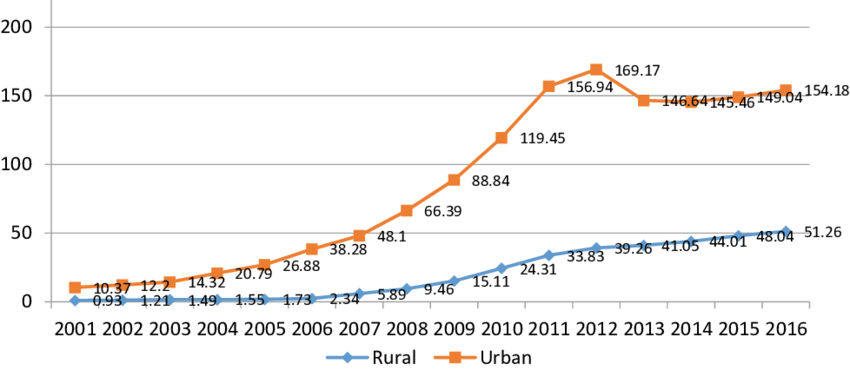

توضیح تصویر: نمودار افزایش تقاضای تله دنتیستری در هند در یک پژوهش معتبر از سالهای 2001 تا 2016